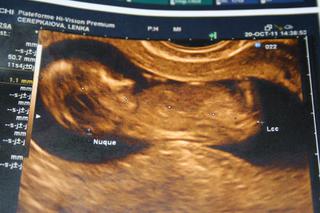

skoro ma odvalilo, ked mi sestricka zobrala 4 skumavky krvi, tlak som mala 100/60 a pan doktor hovori, ze je vsetko v uplnom poriadku. meral nam aj NT, mame 0,9 mm, ze je to v norme a drobec ma cca 6,5 cm (chvilu mal 6,3, potom zas 6,6...)

@lenkalela nádherné, už aj ja chcem mať také foto, ale ešte musím vydržať týždeň